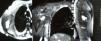

El liposarcoma mixoide de células redondeadas es un tumor habitualmente originado de partes blandas, que raramente encuentra su origen en el plexo braquial. Presentamos un caso muy infrecuente de liposarcoma mixoide de células redondeadas de plexo braquial que fue intervenido quirúrgicamente y que evolucionó favorablemente y sin focalidad neurológica tras 2 años de seguimiento. Es el primer caso publicado de esta estirpe oncológica originado en el plexo braquial.

Myxoid/round cell liposarcoma is a soft tissue sarcoma that is extremely rare in the brachial plexus. We report a case of a myxoid/round cell liposarcoma originating in the brachial plexus that was surgically resected and evolved well, with no deficit or recurrence after 2 years of follow-up. To date, there has been no other case of this sarcoma in the literature.